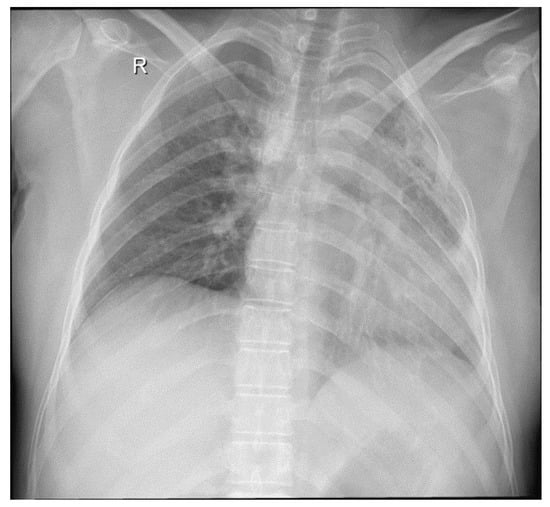

- Radiological evidence of chronic pulmonary lesion;

- Mycological demonstration of Aspergillus fumigates hyphae by microscopy from spu-tum, microscopy and culture from bronchial aspirate, and histopathological evi-dence of the presence of Aspergillus fumigates hyphae with dichotomous branching in the spinal cord biopsy;